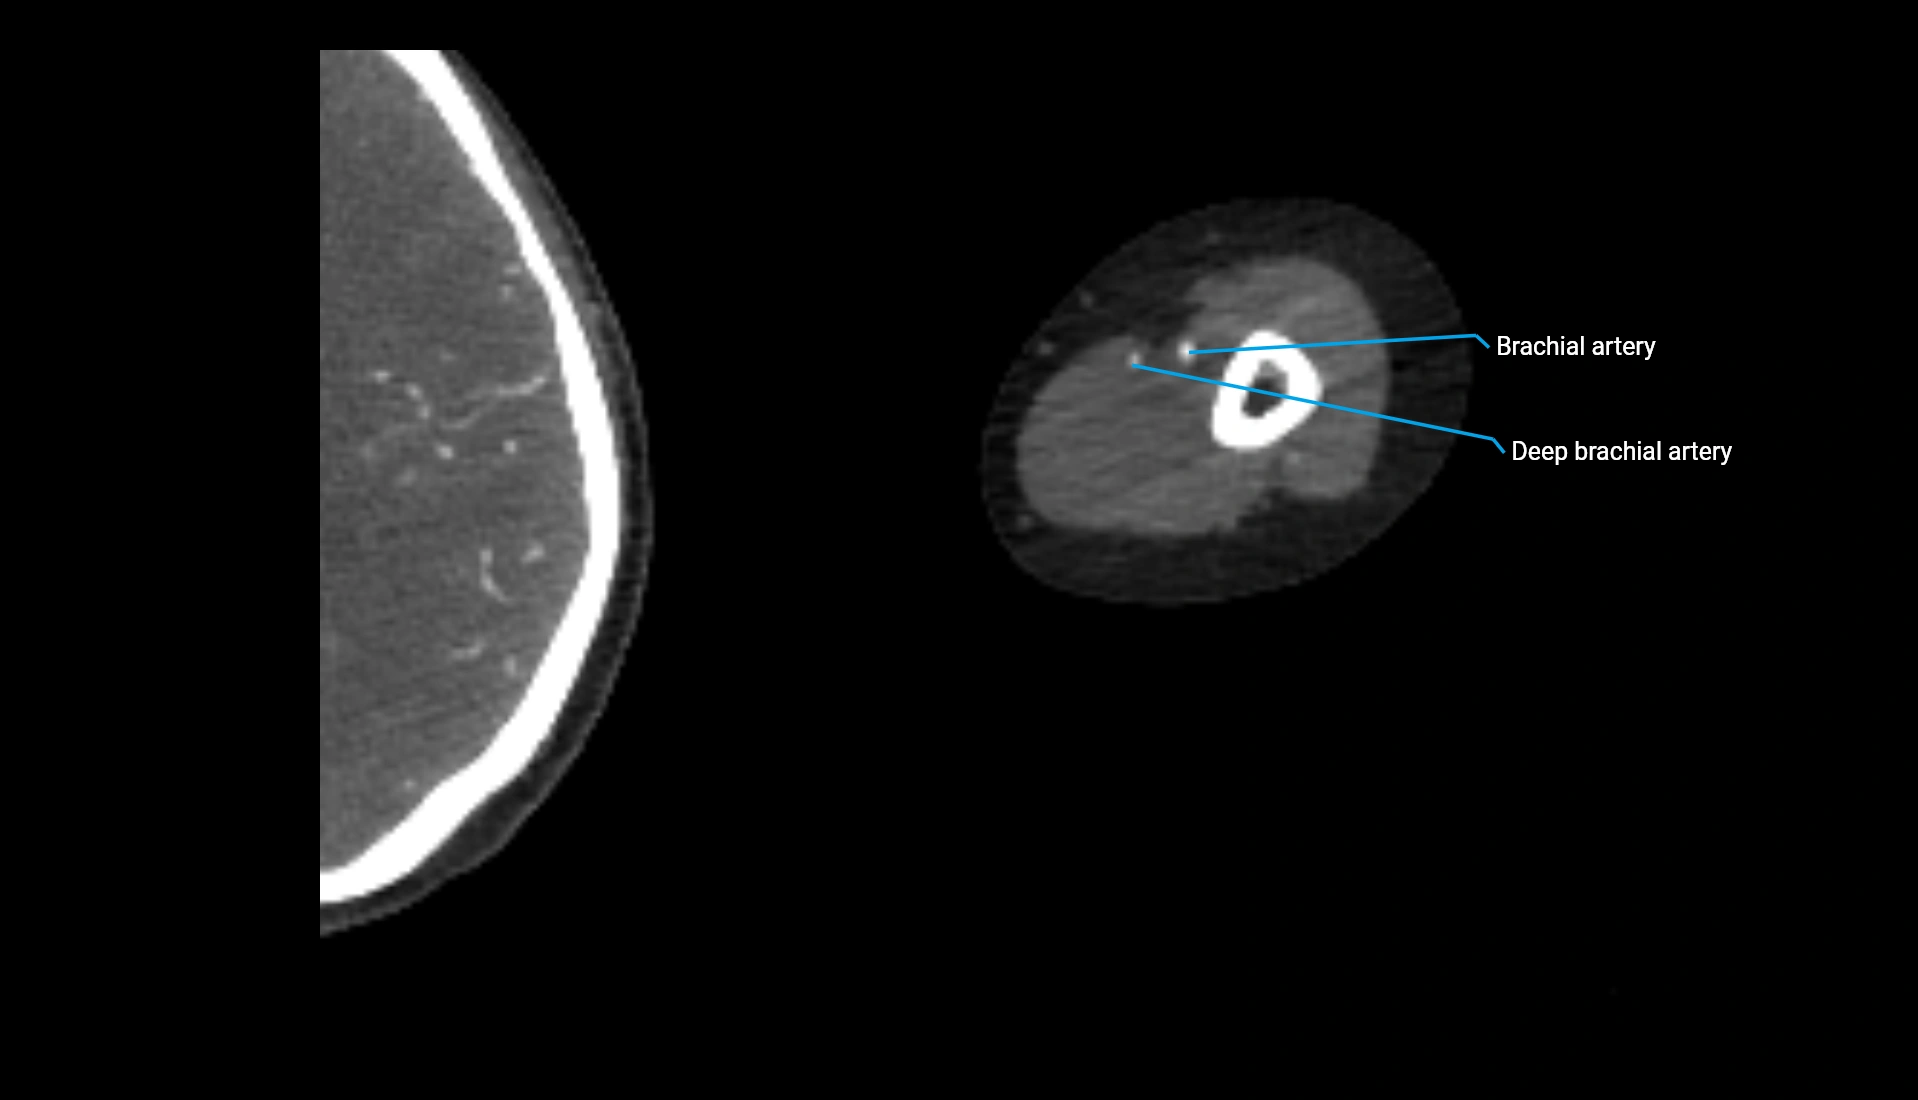

CT Appearance

Non-Contrast CT:

• Cortex: High-density, sharply defined

• Subchondral bone: Dense cancellous matrix

• Articular surface: Smooth concave contour articulating with the capitellum

• Excellent for evaluating bone integrity, alignment, and subtle fractures

Post-Contrast CT:

• Bone: No enhancement

• Joint capsule and synovium: Mild enhancement outlining the joint

• Improves contrast between soft tissues and bony margins

• Useful in detecting subtle joint abnormalities or postoperative changes